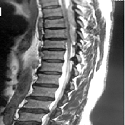

Cricopharyngeal bar

Suresh Chander Sharma, Pirabu Sakthivel

PAMJ. 2017; 27: 288. Published 23 August 2017